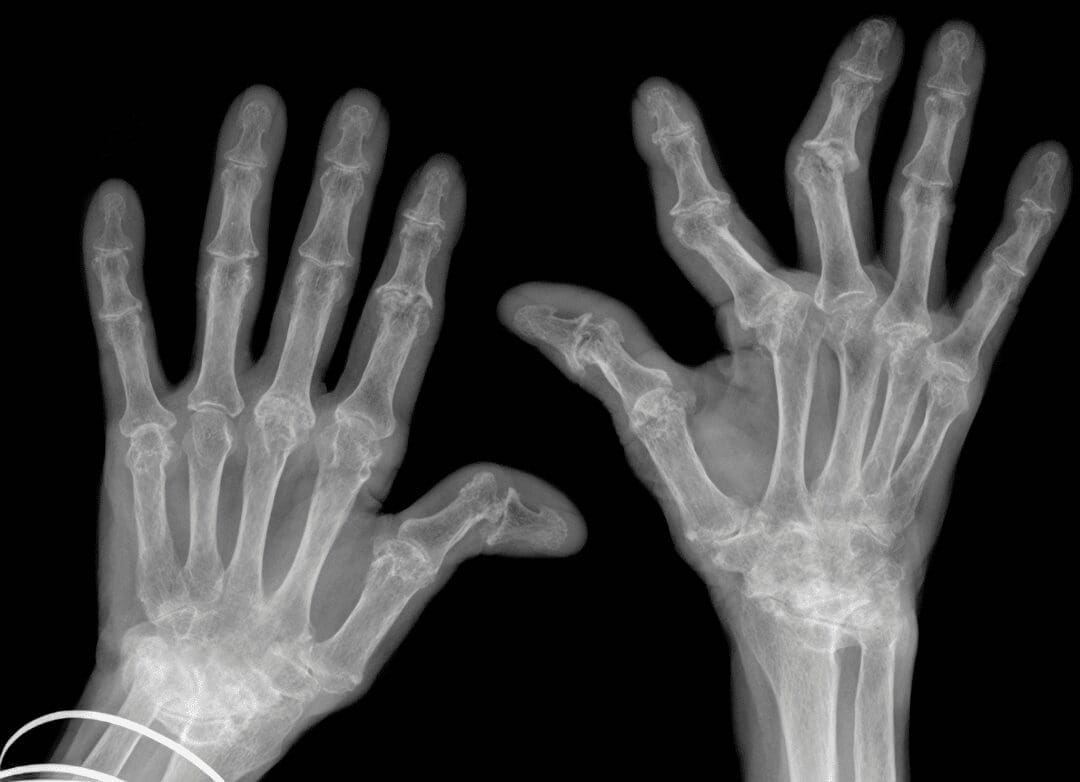

Unlike OA, RA is an autoimmune disease.

This means the immune system, your body’s defense system, mistakenly attacks healthy tissues. In RA, the target is the synovial membrane, the lining of your joints. This chronic inflammation damages joint tissue, causing persistent pain, instability (difficulty maintaining balance), and deformities (changes in the shape of the joint). RA typically affects multiple joints simultaneously, with the hands, wrists, and knees being common targets. It can also extend its reach beyond joints, potentially impacting organs like the lungs, heart, and eyes.